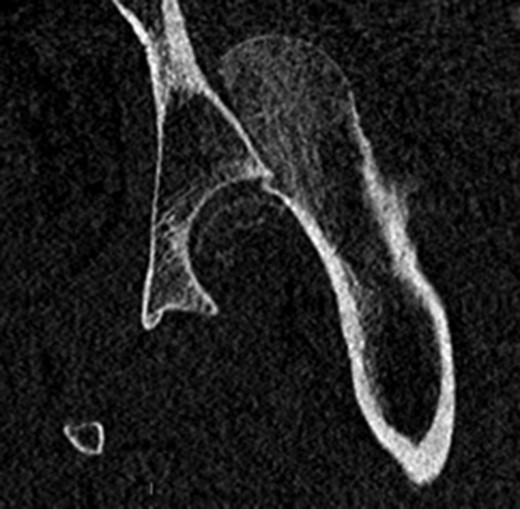

A fit and well man in his 40s had fallen while hiking up a steep hill. He complained of immediate onset, severe left hip pain and inability to move. He was airlifted to our hospital and was found to have shortened externally rotated left leg. Plain X-rays were performed in the emergency department (Fig. 1) identifying isolated fracture–dislocation of the left hip. Computed tomography (CT) was performed while en route to theatre (Figs 2 and 3).

Due to the time involved in the airlift extraction, the hip was dislocated for ~5–6 h. He was attended to by the on-call Consultant Orthopaedic Surgeon, and under general anaesthetic, the hip was reduced with no particular difficulty. The case was referred to the department hip specialist. A further CT scan was performed to assess the position of the fracture to aid in pre-op planning.